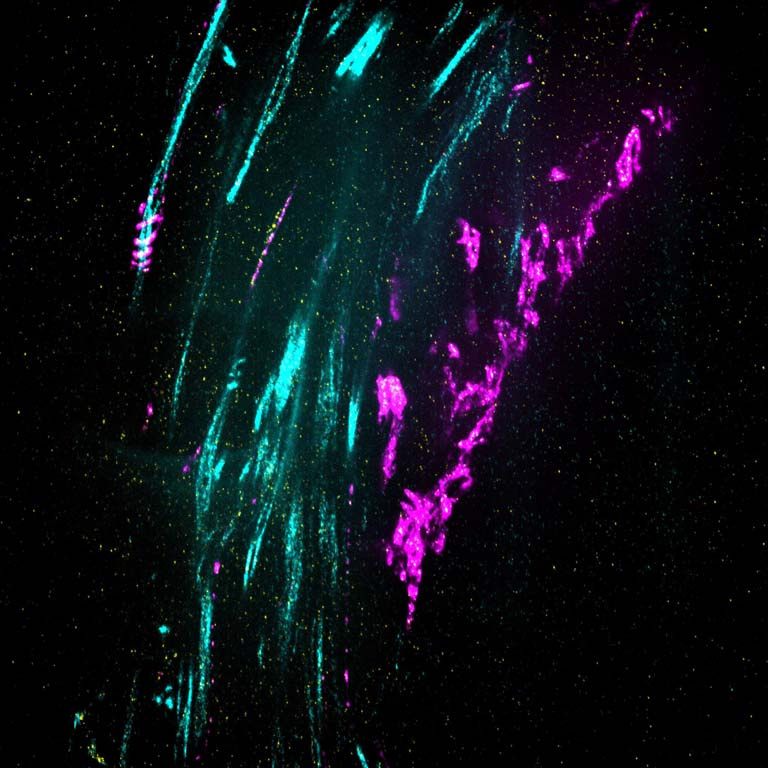

This image shows 800-times-magnified views of a helical amyloid-beta nanostructure (in color magenta) spirally tangling around a bundle of axons (in color cyan) in an Alzheimer’s Disease (AD) mouse model 5xFAD. Interestingly, clusters of sodium ion channels (in yellow) were found co-localizing with these distinct amyloid-beta nanostructures, suggesting intriguing functional relationships between these proteins and potential functional consequences.

Although the misfolding of amyloid-beta (Aβ) in the forms of Aβ plaques is a prominent pathological hallmark of Alzheimer’s Disease (AD), the roles of which remains investigated partially because Aβ plaques is only weakly correlated with the degree of cognitive decline in AD. However, it’s shown that different forms of soluble and insoluble Aβ aggregates including Aβ oligomers, Aβ fibrils etc, may be associated with different disease stages. Therefore, understanding the structural and interaction details of Aβ aggregates could provide mechanistic insights into how different conformations of Aβ induce neurotoxicity.

This DNA-probe-based super-resolution microscopy not only enables previously unseen structural features of Aβ helical nanostructure, it also reveals interaction and position details of this protein.